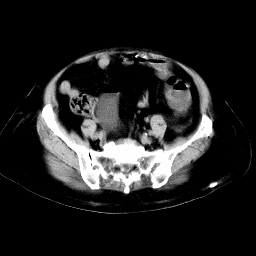

以下是引用arven在2008-11-9 10:13:00的发言:[br]肠壁增厚,形态较规则,支持降结肠炎症改变